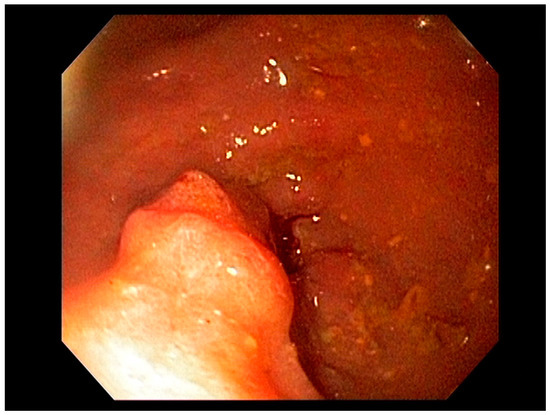

3.2. Endoscopic Resection Techniques for Early-Stage Esophageal Cancer (T1a and T1b)

4.2. Early Gastric Cancer (EGC)